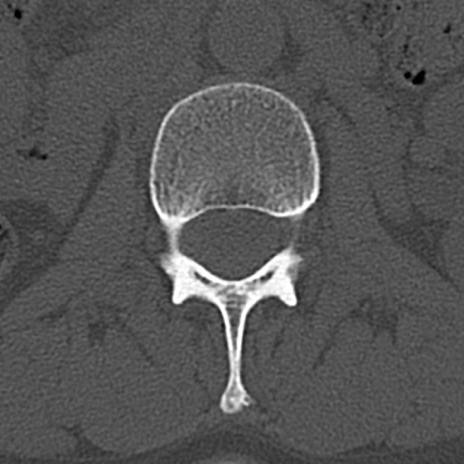

腰椎CT

横断像と矢状断像